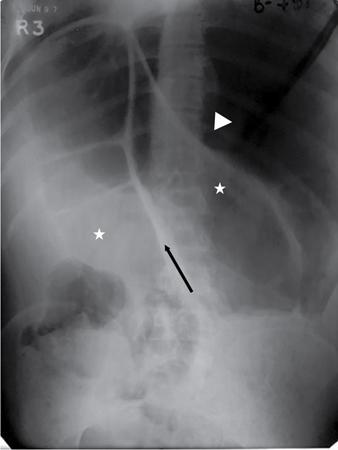

UNDERSTANDING THE ADULT ABDOMINAL RADIOGRAPH: TECHNIQUES AND INTERPRETATION Tanvi Modi Radiography of the abdomen is a common practice for the evaluation of abdominal organs. The anatomy and pathology of digestive, hepatobiliary and genitourinary systems can be assessed using radiographs, either as a stand-alone practice or as a primary imaging modality followed by contrast studies, ultrasound or cross-sectional imaging. In addition, abnormalities of the musculoskeletal or integumentary system can also be deduced on the basis of abdominal radiographs. This chapter intends to give an overview on the techniques and positioning in abdominal radiography as well as interpretation of normal and abnormal features. While superior imaging modalities such as ultrasound, computed tomography (CT), magnetic resonance imaging, capsule endoscopy and the likes have taken over abdominal imaging by and large, radiography still holds a pivotal role in certain situations and conditions, such as: The standard abdominal radiograph is taken in supine position and anteroposterior projection. This is also popularly known as the KUB (kidneys-ureters-bladder) radiograph. Previously, supine as well as erect radiographs were performed in all patients; however, this is not commonly done due to high-radiation dose. For all indications of abdominal radiography, including acute abdomen, supine radiographs are sufficient in terms of radiographic diagnosis, with the exception of perforation for which an erect chest or lateral decubitus radiograph can be performed if there is clinical suspicion. Patient should lie supine on the imaging table with median sagittal plane at right angles to the table and coincident with the midline of the table (Fig. 7.1.1.1). The body is divided into equal right and left halves by the median sagittal which passes through the sagittal suture of the skull. Pelvis should be adjusted so that the anterior superior iliac spines are equidistant from the table top. Gonadal shields, in the case of male patients, should be placed with the upper edge of the shield at the level of pubic symphysis. Although rarely used for female patients, these should be positioned between the anterior superior iliac spines and the pubic symphysis. The centre point of the image receptor should be approximately located at a point 1 cm below the line joining the iliac crests. The X-ray beam should be in a vertical direction, perpendicular to the table top and image receptor at the centre point. Collimation should be such that the soft tissue and subcutaneous region along lateral aspects of the abdominal cavity should be covered within the image. Also, the superior extent involving diaphragm and inferior extent involving the inferior pubic rami is important to look for any lower chest pathologies or any inguinal hernia. 35 × 43 cm (14 × 17 inches) in portrait orientation. On an average, abdominal radiograph exposes a patient to a dose of approximately 1.5 mSv, which is equivalent to 75 chest radiographs or 1/6th dose of a standard CT of the abdomen. The entrance skin dose is approximated to be 4 mGy. At such an effective dose, the additional lifetime risk of fatal cancer is 1 in 30,000. The exposure time is kept short. Patient is asked to exhale completely and hold their breath, with exposure taken at this point of full expiration to ensure imaging of abdominal organs in their natural positions. Modifications of this technique can be made depending on patient habitus and clinical condition. Kilovoltage peak (kVp) should be set to allow adequate visualization of abdominal soft tissue structures as well as semiopaque renal and biliary calculi. Average kVp is set at 70–85 kV. 102 cm (40 inches) Grids are commonly used to reduce scatter radiation. Placement of side marker on the image receptor at the time of radiographic exposure is essential. Bowel pattern depiction should be such that there is minimal lack of sharpness. Standard guidelines for abdominal radiography dictate that the radiograph should extend from the diaphragm up to the level of inferior pubic rami and must include the lateral abdominal wall musculature. The abdomen is divided into four quadrants on the basis of two perpendicular lines (Fig. 7.1.1.7). The vertical line passes through the mid sagittal plane and crosses the umbilicus and symphysis pubis. The horizontal line is a transverse line across the umbilicus at 90 degrees to the vertical line and is situated at the level of L4–L5 intervertebral disc. The quadrants are as follows: Another division system is dividing the abdominopelvic cavity into nine regions using two vertical and two horizontal planes (Fig. 7.1.1.8). The vertical planes, also known as the right and left lateral planes, are parallel to the midsagittal plane between midline and anterosuperior iliac spines on either side. Of the two horizontal planes, the upper transpyloric plane is at the level of lower border of L1 and the lower transtubercular plane is at the level of L5. The nine regions are: On a standard radiograph, the exposure should be such that the stomach, bowel loops, outlines of liver, spleen, kidneys, psoas muscles should be well identified. Also, lumbar transverse processes should be seen. Arch of the pubic symphysis should be visible to evaluate bladder region. A well-centred film without rotation will demonstrate bilaterally symmetrical lower ribs, iliac wings, ischial spines and obturator foramina. Different structures seen on an abdominal radiograph can be classified into five basic densities: Identification of different structures depends on the relative degree of contrast between their densities. The demarcation is clearer in chest and is diminished in abdomen due to relative similar soft tissue density of various structures. On a normal radiograph, relatively large amounts of gas in stomach and colon with minimal small bowel gas can be seen. Further, colonic gas can vary from negligible to extensive, mimicking obstruction pattern; however, usually the gas is enough to delineate colonic haustral pattern. Faecal matter gives a mottled appearance to colonic gas. Short-air fluid levels on an erect radiograph may be seen even in normal cases. The normal appearance of small bowel loops on an abdominal radiograph follows the rule of threes: Stomach is seen in the left upper quadrant and is visualized when distended with air. It is commonly seen extending from T11 to L2 level. Common feature identifying the stomach is the fundal gas which is usually seen as an air fluid level within the gastric lumen. Small bowel loops are distributed to the centre of the abdominal cavity and large bowel loops are peripheral. Duodenum is predominantly situated in right upper quadrant. It extends to left upper quadrant in the region of duodenojejunal flexure. Jejunum occupies the left upper and lower quadrants and is easily identified due to the presence of thick, numerous, closely spaced valvulae conniventes (Fig. 7.1.1.9A). The ileum occupies both lower quadrants and extends into right upper quadrant. Ileum has few and less prominent valvulae as compared to jejunum (Fig. 7.1.1.9B). Ascending and descending colon are retroperitoneal and have relatively fixed positions along lateral aspect of the abdominal cavity on either side. Transverse and sigmoid colon, on the other hand, may have a variable position due to their mobility along mesocolon and redundant pattern. These can be identified with confidence on account of haustrations and faecal matter (Fig. 7.1.1.10). Haustrations are usually well seen in ascending and transverse colon and poorly delineated beyond splenic flexure. Caecum is in the right lower quadrant, though it may be mobile or pulled up. Rectal gas is usually seen in the midline at the level of pelvis and its presence rules out large bowel obstruction. All these positions may vary due to anatomical conditions such as malrotation or pathological conditions, for example volvulus. Liver, spleen and renal outlines cannot be completely traced with precision due to the overlap by bowel loops. On a frontal projection, the liver appears as a triangular structure occupying right and left hypochondrium and epigastric region. Occasionally, the right lobe may be seen extending lower than the right renal shadow. This is a normal variant known as Reidel’s lobe. Gall bladder is situated in the posterior and inferior region of the liver and any pathology of the gall bladder should be looked for in this region. On a lateral radiograph, the gall bladder is anterior to the midcoronal plane. This helps in distinguishing gall bladder calculi from renal calculi, which will be more posteriorly situated. Spleen is seen in left upper quadrant/left hypochondrium, flushed to left lower ribs and left hemidiaphragm. Pancreas is present in the epigastric region (right and left upper quadrants) and is usually not identified in the absence of a pathology. The kidneys are bean-shaped retroperitoneal organs which are seen on either side of the vertebral column and lateral to psoas muscles. Due to the presence of liver on the right side, this kidney is slightly lower in position as compared to its contralateral counterpart. The visualization of kidneys on radiographs is facilitated by the surrounding fatty capsule. Kidneys lie between T11–12 and L2 level, with left kidney 1 cm higher than the right. Psoas muscle shadow can be normally seen along lateral aspect of lumbar spine bilaterally and is mildly concave (Fig. 7.1.1.11). Abdominal wall muscles are not routinely assessed on radiography; however, inclusion of lateral abdominal wall (muscles as well as subcutaneous plane) is a must while performing radiography. The flank stripe or the properitoneal fat stripe is a fat density linear concavity seen along lateral abdominal wall (Fig. 7.1.1.11). It is bound by the paracolic gutters and air-filled ascending and descending colon. All the solid organs in the abdomen are identified due to the fat density outlining them. Distortion of these fat lines helps in identifying organomegaly or focal mass lesions. The dome of urinary bladder is outlined by fat, which aids in differentiating its density from other soft tissue structures of the pelvis. Not all calcifications seen on abdominal radiograph are abnormal. Some may depict age-related changes such as vascular calcifications involving abdominal aorta, pelvic vessels, splenic artery in the region of left upper quadrant. Within the pelvis, phleboliths may be seen and mistaken for urinary calculi. Assessment of lumbosacral spine, iliac bones and femoral heads can be made on the basis of plain radiography. Degenerative changes may be commonly seen. Lower ribs can also be evaluated for pathologies. Dilated small bowel loops with rounded soft tissue density in midline over umbilical region suggests obstruction secondary to umbilical hernia. Pneumoperitoneum must be looked for in all cases of acute abdomen. While erect chest and left lateral decubitus radiographs can detect even 1 mL of free air, there are multiple signs on supine radiograph to suggest this diagnosis, for example Rigler’s sign, falciform ligament sign, football sign (Figs. 7.1.1.24 and 7.1.1.25). Retroperitoneal perforation may demonstrate air outlining psoas muscles and retroperitoneal organs. Small amount of free air may persist in the abdominal cavity up to 3 weeks after surgery, although it usually resolves within a week. Clinical history is important in such cases. Air foci within the bowel wall may represent bowel ischaemia/strangulation. Linear gas patterns in right hypochondrium may be due to two causes, that is pneumobilia and pneumoporta. The former can be seen normally postbiliary surgery, sphincterotomy, ERCP or in the case of abnormal fistulous communication between bowel and biliary tree (Fig. 7.1.1.26A). Pneumoporta (Fig. 7.1.1.26B) is a red flag and warrants further investigation to look for conditions such as mesenteric ischaemia and toxic megacolon. Pneumobilia is more centrally located whereas air shadows in pneumoporta are seen reaching up to periphery of liver. Air foci over renal shadows (Fig. 7.1.1.27), gall bladder or pancreas, in the absence of recent procedural history, suggest fulminant infection and mandate urgent intervention. Central midline calcific foci between T9 and T12 vertebrae can be attributed to calcific pancreatitis (Fig. 7.1.1.28). In the left upper quadrant, areas of calcification seen involving a shrunken spleen may be seen in autosplenectomy. In right upper quadrant, calcified gall stones may be seen. These tend to be small, multiple, uniformly circumscribed and ring-like in appearance with central translucency (Fig. 7.1.1.29A). Mercedes Benz sign, a triradiate pattern of gas lucency, is associated with gallstones. In contrast, renal calculi are more commonly solitary, irregular, of homogenous density, conform to renal calyceal or pelvic outline (Fig. 7.1.1.29B) and are sometimes of staghorn configuration. On lateral view, the gall stones are more anteriorly located as compared to renal calculi, which may be partly superimposed on lumbar vertebrae. Ureteric calculi tend to overlap bony structures such as lumbar transverse processes (Fig. 7.1.1.29B) or sacroiliac joints. Extensive or patchy, curvilinear calcification of gall bladder wall is known as porcelain gall bladder which is often associated with malignant transformation. Calcification involving adrenal glands may be secondary to infection or haematoma, or a congenital condition known as Wolman’s disease where there is bilateral involvement. Discontinuous discrete midline tram track calcification in the abdomen may indicate atherosclerotic changes in abdominal aorta and branch vessels. However, when the calcification is in a globular pattern and seen below the level of L2 vertebra, aortic aneurysm should be suspected (Fig. 7.1.1.30). Appendicoliths, though not commonly seen, may sometimes be detected in right iliac region. Pelvic calcifications: vesical calculi, distal ureteric or vesicoureteric junction calculi, calcified fibroids, ovarian dermoid with tooth-like calcifications (Fig. 7.1.1.31) may be the cause of abdominal pain and should be diligently looked for. Vesical calculi are usually more large and central in location whereas calcification due to fibroids may be more lateral. Schistosomiasis is another cause of bladder wall calcification, as is calcification of bladder tumours. Phleboliths tend to be bilaterally symmetrical, with a lucent centre unlike ureteric calculi. While it is believed that phleboliths are located below the level of ischial spines and ureteric calculi above, this is not always true and should be confirmed with CT. Fluid may collect adjacent to properitoneal fat line, forming a linear soft tissue density separating the fat line from the ascending or descending colon. Hellmer’s sign demonstrates medial displacement of lateral edge of liver (hepatic angle), due to fluid collection or ascites. Gross ascites may appear as generalized abdominal haziness or diffuse increased density of pelvis. Abscesses can involve any solid organ and in such cases may be difficult to demonstrate on plain radiography alone. Enlargement of organ or faint gas densities within can be suggestive of the same. In the case of peritoneal abscess, mottled density due to air, fluid and necrotic contents point towards this diagnosis, especially in right iliac fossa in association with appendicitis. Retroperitoneal abscess, similar to any retroperitoneal mass, may cause displacement of retroperitoneal structures (Fig. 7.1.1.32). Subdiaphragmatic abscesses may show concomitant ipsilateral pleural effusion (Fig. 7.1.1.33). These should be differentiated from Chilaiditi syndrome. Fluid and soft tissue lesions present with the same density on radiographs. While it is difficult to characterize the lesion and organ of origin, clues for the same can be provided by organomegaly (Fig. 7.1.1.34), distortion of fat surrounding solid organs, displacement of bowel loops or solid organs. For example, a retroperitoneal lesion may cause anterior or inferior displacement of kidney, a pelvic mass may cause upward displacement of small bowel loops. Different densities such as fat or calcification may help in identifying organ of origin (e.g. fat and tooth densities seen in ovarian dermoid). Convexity of margins of psoas muscle on an abdominal radiograph can be due to haematoma, abscess or intramuscular tumour. Radiographs are performed for the initial diagnosis of foreign body in the abdomen including type, number of foreign bodies, location, size and shape (Fig. 7.1.1.35). Radiolucent foreign bodies such as wood, plastic, chicken bones will not be easily identified on radiography. Low kVp (65–70 kVp) can increase contrast and help identify these objects. In addition to an abdominal radiograph, chest radiography is also performed to exclude aspiration or oesophageal location of foreign body. Ingested or introduced foreign bodies may cause complications such as obstruction, perforation, fistula formation and sepsis. Hence, once their presence is confirmed, follow up radiography must be performed until they are eliminated. One must look for fractures/dislocation injuries involving the vertebrae or pelvic bones, especially after history of trauma. Lucent expansile lesions or sclerotic bony deposits which represent neoplasms, absent pedicle sign in cases of metastasis, metabolic bony changes such as rugger jersey appearance, Paget’s disease, arthropathies such as ankylosing spondylitis with bamboo spine appearance and sacroiliitis (Fig. 7.1.1.36) are some of the conditions which may be diagnosed based on an abdominal radiograph. Overlap of bowel loops over iliac blades may lead to a misdiagnosis of lucent lesions and should be evaluated with caution. Basal pneumonia may be the cause of acute abdominal pain and should be looked for in abdominal radiography. Similarly, pleural effusion, pericardial effusion, calcified pleural plaques, achalasia, interstitial fibrosis are few other findings that can be seen in lower chest on an abdominal radiograph. Basilar atelectasis can give a deceptive appearance of pneumoperitoneum (Fig. 7.1.1.37). Surgical clips, commonly in right hypochondrium after cholecystectomy, drainage tubes, ventriculoperitoneal shunts, femoral line catheters, IVC filters, stents (vascular, renal, biliary) (Fig. 7.1.1.38), stoma bags, contraceptive devices are some structures that may be seen in an abdominal radiograph. Correct knowledge of patient history and normal locations of these structures prevents misdiagnosis. Certain artefacts may be projected upon the radiograph due to surface structures such as trouser buttons, body piercing, sequins over clothing and should not be considered as a pathology. Multiple skin surface nodules in cases of neurofibromatosis, soft tissue focal swellings, such as abscesses, lipomas, haematomas, desmoid tumours and malignant lesions may be incidentally seen on radiography. These can be further evaluated using ultrasound or CT. Subcutaneous emphysema is another finding that may be seen in lower abdominal wall secondary to retroperitoneal perforation or diffusely along abdominal wall in the case of bowel perforation (Fig. 7.1.1.39). Foreign bodies such as bullets and pins may be seen lodged in abdominal wall. A systematic approach to abdominal radiographs is important for accurate diagnosis as follows: Despite the development of newer techniques for imaging of the abdomen, plain radiography still holds an important place in the initial assessment of acute abdomen. Positive and negative findings on an abdominal radiograph can direct further investigation. Ideal positioning, recognition of normal appearances and keen scrutiny for pathologies is a sine qua non for radiologists reading a plain film of the abdomen. OESOPHAGOGRAM Padma V. Badhe, Vikram Reddy, Sultan Moinuddin Shaukatali, Zillani Alam, Ravi Varma, Abhishek Bairy, Dasari Ravikiran, Revati Tekwani, Soniya Patankar, Megha Nair, Gautham Shankar Oesophagogram is the process of obtaining radiological images and simultaneous motion recording to evaluate function and disorders of pharynx, oesophagus and proximal stomach. Oesophagogram is usually done primarily to evaluate dysphagia. Some of the common indications are oesophageal motility disorders, strictures, gastro-oesophageal reflux disease (GERD) and suspected masses. It can also be used to detect uncommon anomalies like vascular rings/slings and aberrant anatomy. It also helps to evaluate further in cases where there is inability to pass upper GI scope. Double-contrast oesophagogram is mainly indicated in early mucosal disease like erosion, polyp, infection and tumours. If a motility disorder is suspected, dynamic technique (e.g. videofluoroscopy) is used for dysphagia or aspirations in cases of stroke, neuromuscular disorders, post head and neck surgery or radiation. Barium oesophagogram is contraindicated in suspected cases of perforation and tracheoesophageal fistula, aspiration, rarely if there is hypersensitivity to barium suspensions. It is also contraindicated in suspected oesophageal perforation where a water-soluble contrast agent is more suitable. However, ionic water-soluble contrast agent is better avoided in cases of aspiration or fistula with airway. The contrast examination of the pharynx is dangerous in cases of acute epiglottitis and must be ruled out on plain radiograph. An 80% w/v barium suspension is used in full column views. However, 200%–250% w/v barium suspensions is usually required for mucosal relief films. The barium sulphate mixture is fed to the patient either by spoon, by glass, or through a drinking straw, depending on its consistency. In videofluoroscopy, the pharyngeal phase of swallowing is usually safer with barium pudding than with thick barium and safer with thick barium than with thin barium. However, if the major abnormality is poor pharyngeal contraction leading to stasis in the piriform sinus (and epiglottic tilt is normal), a thin liquid is safer. Epiglottic motility is better assessed with thin barium because thick barium often obscures the epiglottic tip. Fluoroscopic equipment capable of cine fluoroscopy and capability for rapid sequence spot images (high frame rate) is needed for this examination, Barium suspension, straw, glass, Lead apron and radiation protective equipment. The patients are instructed to fast after midnight before the day of the examination. The pharynx should be made as dry as possible during the examination as high-density barium adheres to dry pharyngeal mucosa. Activities like smoking, chewing gum and lozenges must be abstained before the procedure as they impair barium coating by increasing the salivary secretion. Regular oral medications must be taken with sips of water; however, insulin must be skipped on the morning of examination. The major principles of a good oesophagogram includes mucosal coating, distension and projection. A routine oesophagogram consists of screening of the oral, pharyngeal and oesophageal phases of swallowing, single and double-contrast examination of pharynx, single contrast, double-contrast and mucosal relief views of the oesophagus. In cases of dysphagia, the examination is tailored depending on whether the symptoms are either pharyngeal or oesophageal and initial fluoroscopic findings. If patients’ symptoms are suggestive of oral or pharyngeal disorder then pharynx is evaluated first. Similarly, if patient is suspected to have thoracic oesophageal disease then, double-contrast examination of the oesophagus is performed before the pharyngeal evaluation. During an oesophagogram the positioning of the patient varies according to the type of examination (Table 7.1.2.1).